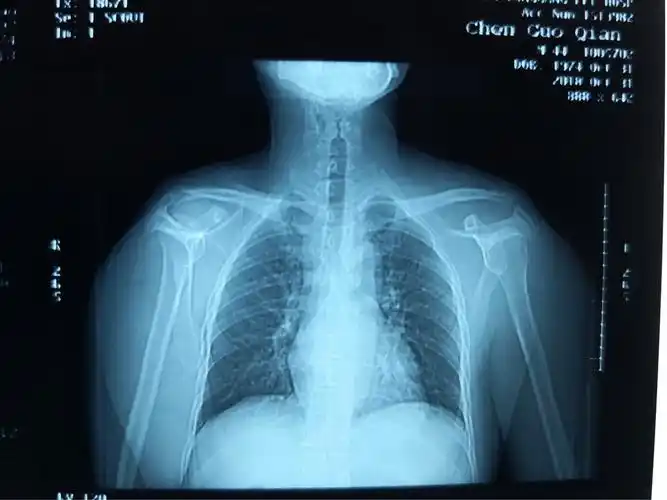

左肩锁关节脱位